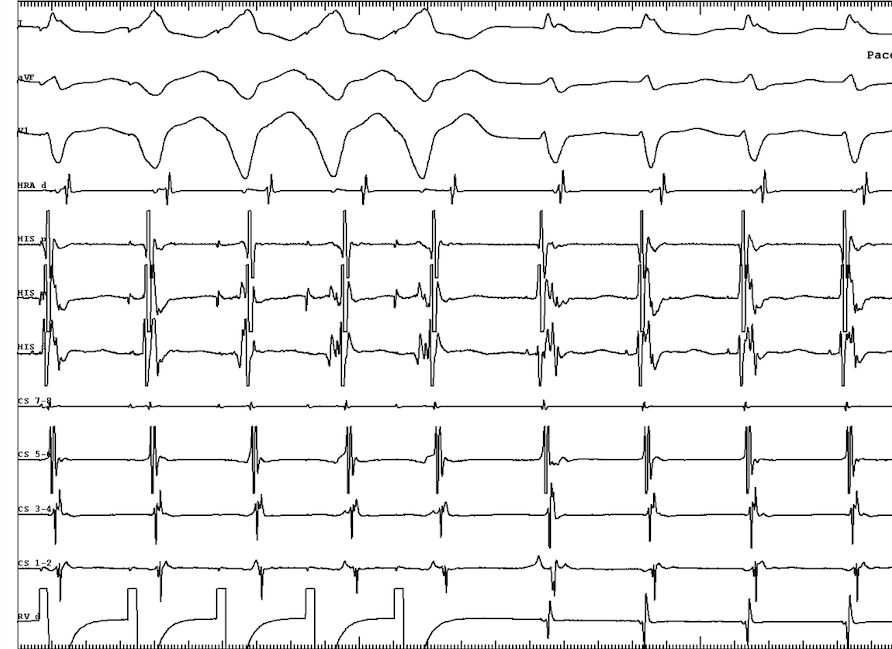

Entrainment from base (cPPi-TCL 80)

entrainment_base.jpg

Entrainment from apex (PPI-TCL 96)

entrainment.jpg

PVC on His

pvc.jpg

Diagnosis

• Concealed nodoventricular AP

• Orthodromic tachycardia

• Successful ablation at RIE